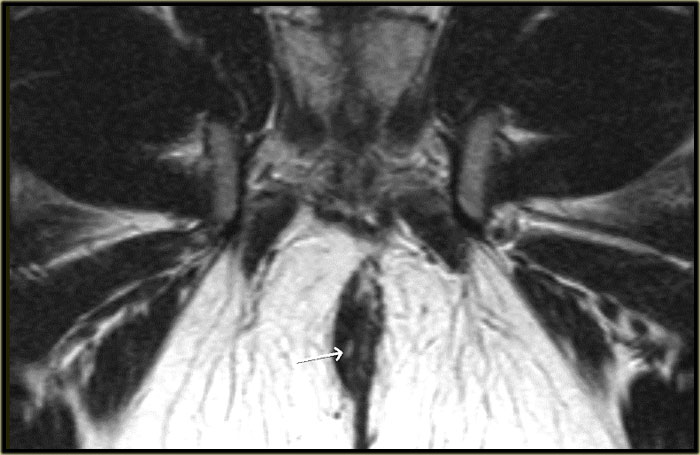

Rò liên cơ thắt

Bên trái là hình ảnh cắt ngang chuỗi xung T2W có và không có xóa mỡ.

Một đường rò liên cơ thắt nằm ở vị trí 6 giờ.

Tiếp tục xem hình ảnh mặt phẳng coronal.

Trên hình ảnh coronal, đường rò chạy xuống phía dưới về phía da.

Không có sự kết nối với cơ thắt ngoài.

Bên trái là hình ảnh coronal của một bệnh nhân khác có rò liên cơ thắt.